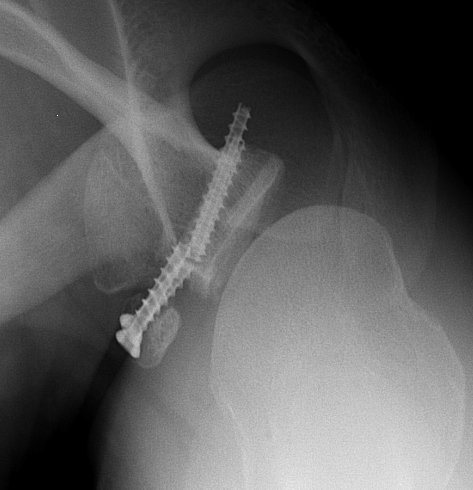

Bristow versus Latarjet

- 66 Bristow procedures versus 35 Latarjet procedures evaluated with CT

- bone union: 97% Latarjet, 73% Bristow

- bone resorption: 100% Latarjet, 6% Bristow

Fixation methods

Thamrongskulsiri et al Clin Orthop Surg 2023

- systematic review of fixation with screws v cortical button

- significantly lower recurrence rates with screw fixation

Traditional versus congruent arc Latarjet

- systematic review

- traditional latarjet: lower incidence fibrous or nonunion

- congruent arc: improved return to sport, recurrent instability and revision surgery for recurrent instability